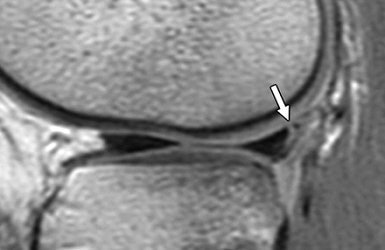

| A 15-year-old girl with originally missed longitudinal peripheral tear of posterior horn of lateral meniscus seen on retrospective review. Tear was repaired with sutures. Sagittal fast spin-echo proton density-weighted image shows peripheral longitudinal tear with vertical orientation (arrow). De Smet AA, Mukherjee R, "Clinical, MRI, and Arthroscopic Findings Associated With Failure to Diagnose a Lateral Meniscal Tear on Knee MRI" (AJR 2007; 190:22-26). |